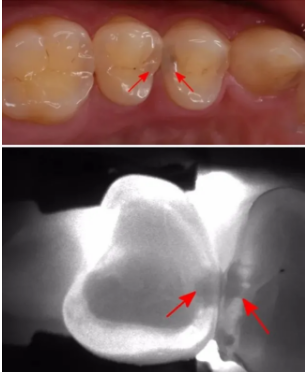

△看似完好的兩顆牙其實已經(jīng)齲壞了

因為,有些齲齒用肉眼并不能直接觀察到,它們不存在于表面,而是隱藏在深處。初期一般沒有明顯癥狀,常常難以被注意到;等到為人所察覺時,往往就已經(jīng)爛得有些深了。若得不到及時治療,最終會形成牙髓炎或根尖周病,進而影響生活質(zhì)量。對付這種隱蔽的口腔健康威脅,最有效的辦法就是定期進行口腔檢查。